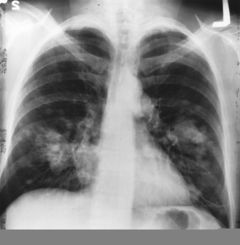

| Cross section of a human lung. The white area in the upper lobe is cancer; the black areas are discoloration due to smoking. | |

- الأشعة السينية

- مسح مقطعي (الأشعة المقطعية)